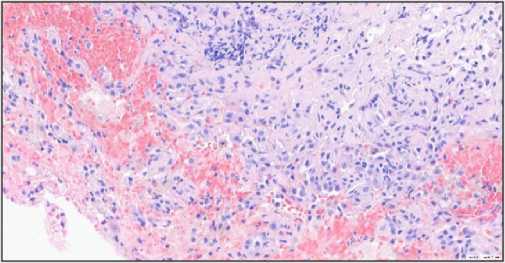

При посмертном гистологическом исследовании опухоль средостения и её метастазы имели солидное строение и состояли из атипичных синцитиотро-фобластов (крупные плеоморфные с насыщенной эозинофильной цитоплазмой и со множественными гиперхромными ядрами с различимыми ядрышками) и цитотрофобластов (полигональные клетки с круглыми ядрами, выраженными ядрышками и прозрачной или эозинофильной цитоплазмой) (рис. 2). Отмечалась высокая митотическая активность опухолевых клеток. Опухоль также имела многочисленные некро- зы. При тотальном гистологическом исследовании яичек патологических очагов не выявлено, паренхима обычного гистологического строения.

Рис. 2. Метастазы в правой почке: a - макроскопически на разрезе темно-красные солидные очаги опухоли; b – микроскопически выявлены атипичные синцитио и цитотрофобласты (гематоксилин и эозин, ×40)